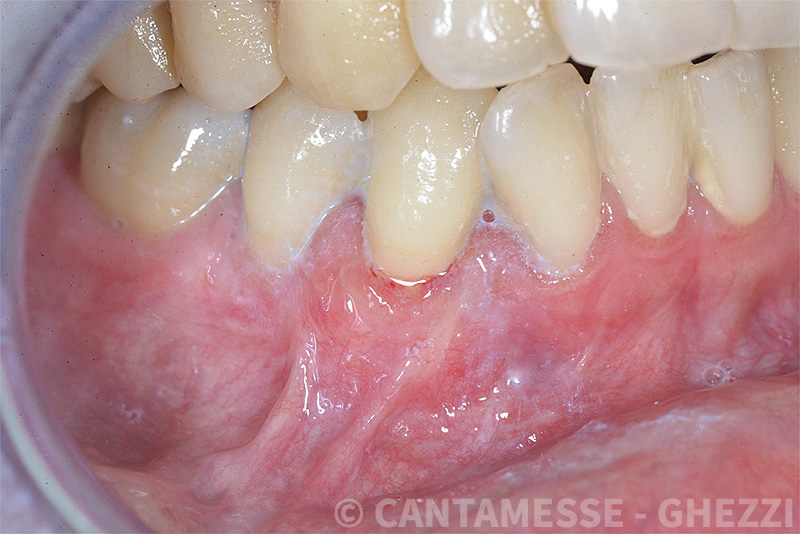

PREMESSA: in seguito all’estrazione dell’incisivo laterale superiore di destra, resasi necessaria per cause batteriche, si decide di affrontare il caso con il posizionamento di un impianto in sostituzione dell’elemento mancante dopo guarigione del sito infetto. Con tecniche rigenerative sia dei tessuti ossei mancanti a causa dell’infezione pregressa, sia dei tessuti gengivali che appaiono inizialmente troppo spostati in alto, si ripristina una corretta morfologia delle parabole (contorni) gengivali e delle papille interdentali (triangoli di gengiva tra due denti vicini).

Vengono utilizzati 2 tipi di provvisori: il primo, cementato ai denti vicini, viene utilizzato dal momento dell’estrazione del dente fino ad impianto osteointegrato (circa 6 mesi); il secondo, avvitato direttamente all’impianto, ha una funzione di prova estetica ma soprattutto di guida per la maturazione dei tessuti gengivali peri-implantari portandoli verso la maturazione completa prima di posizionare la corona finale in disilicato di litio.